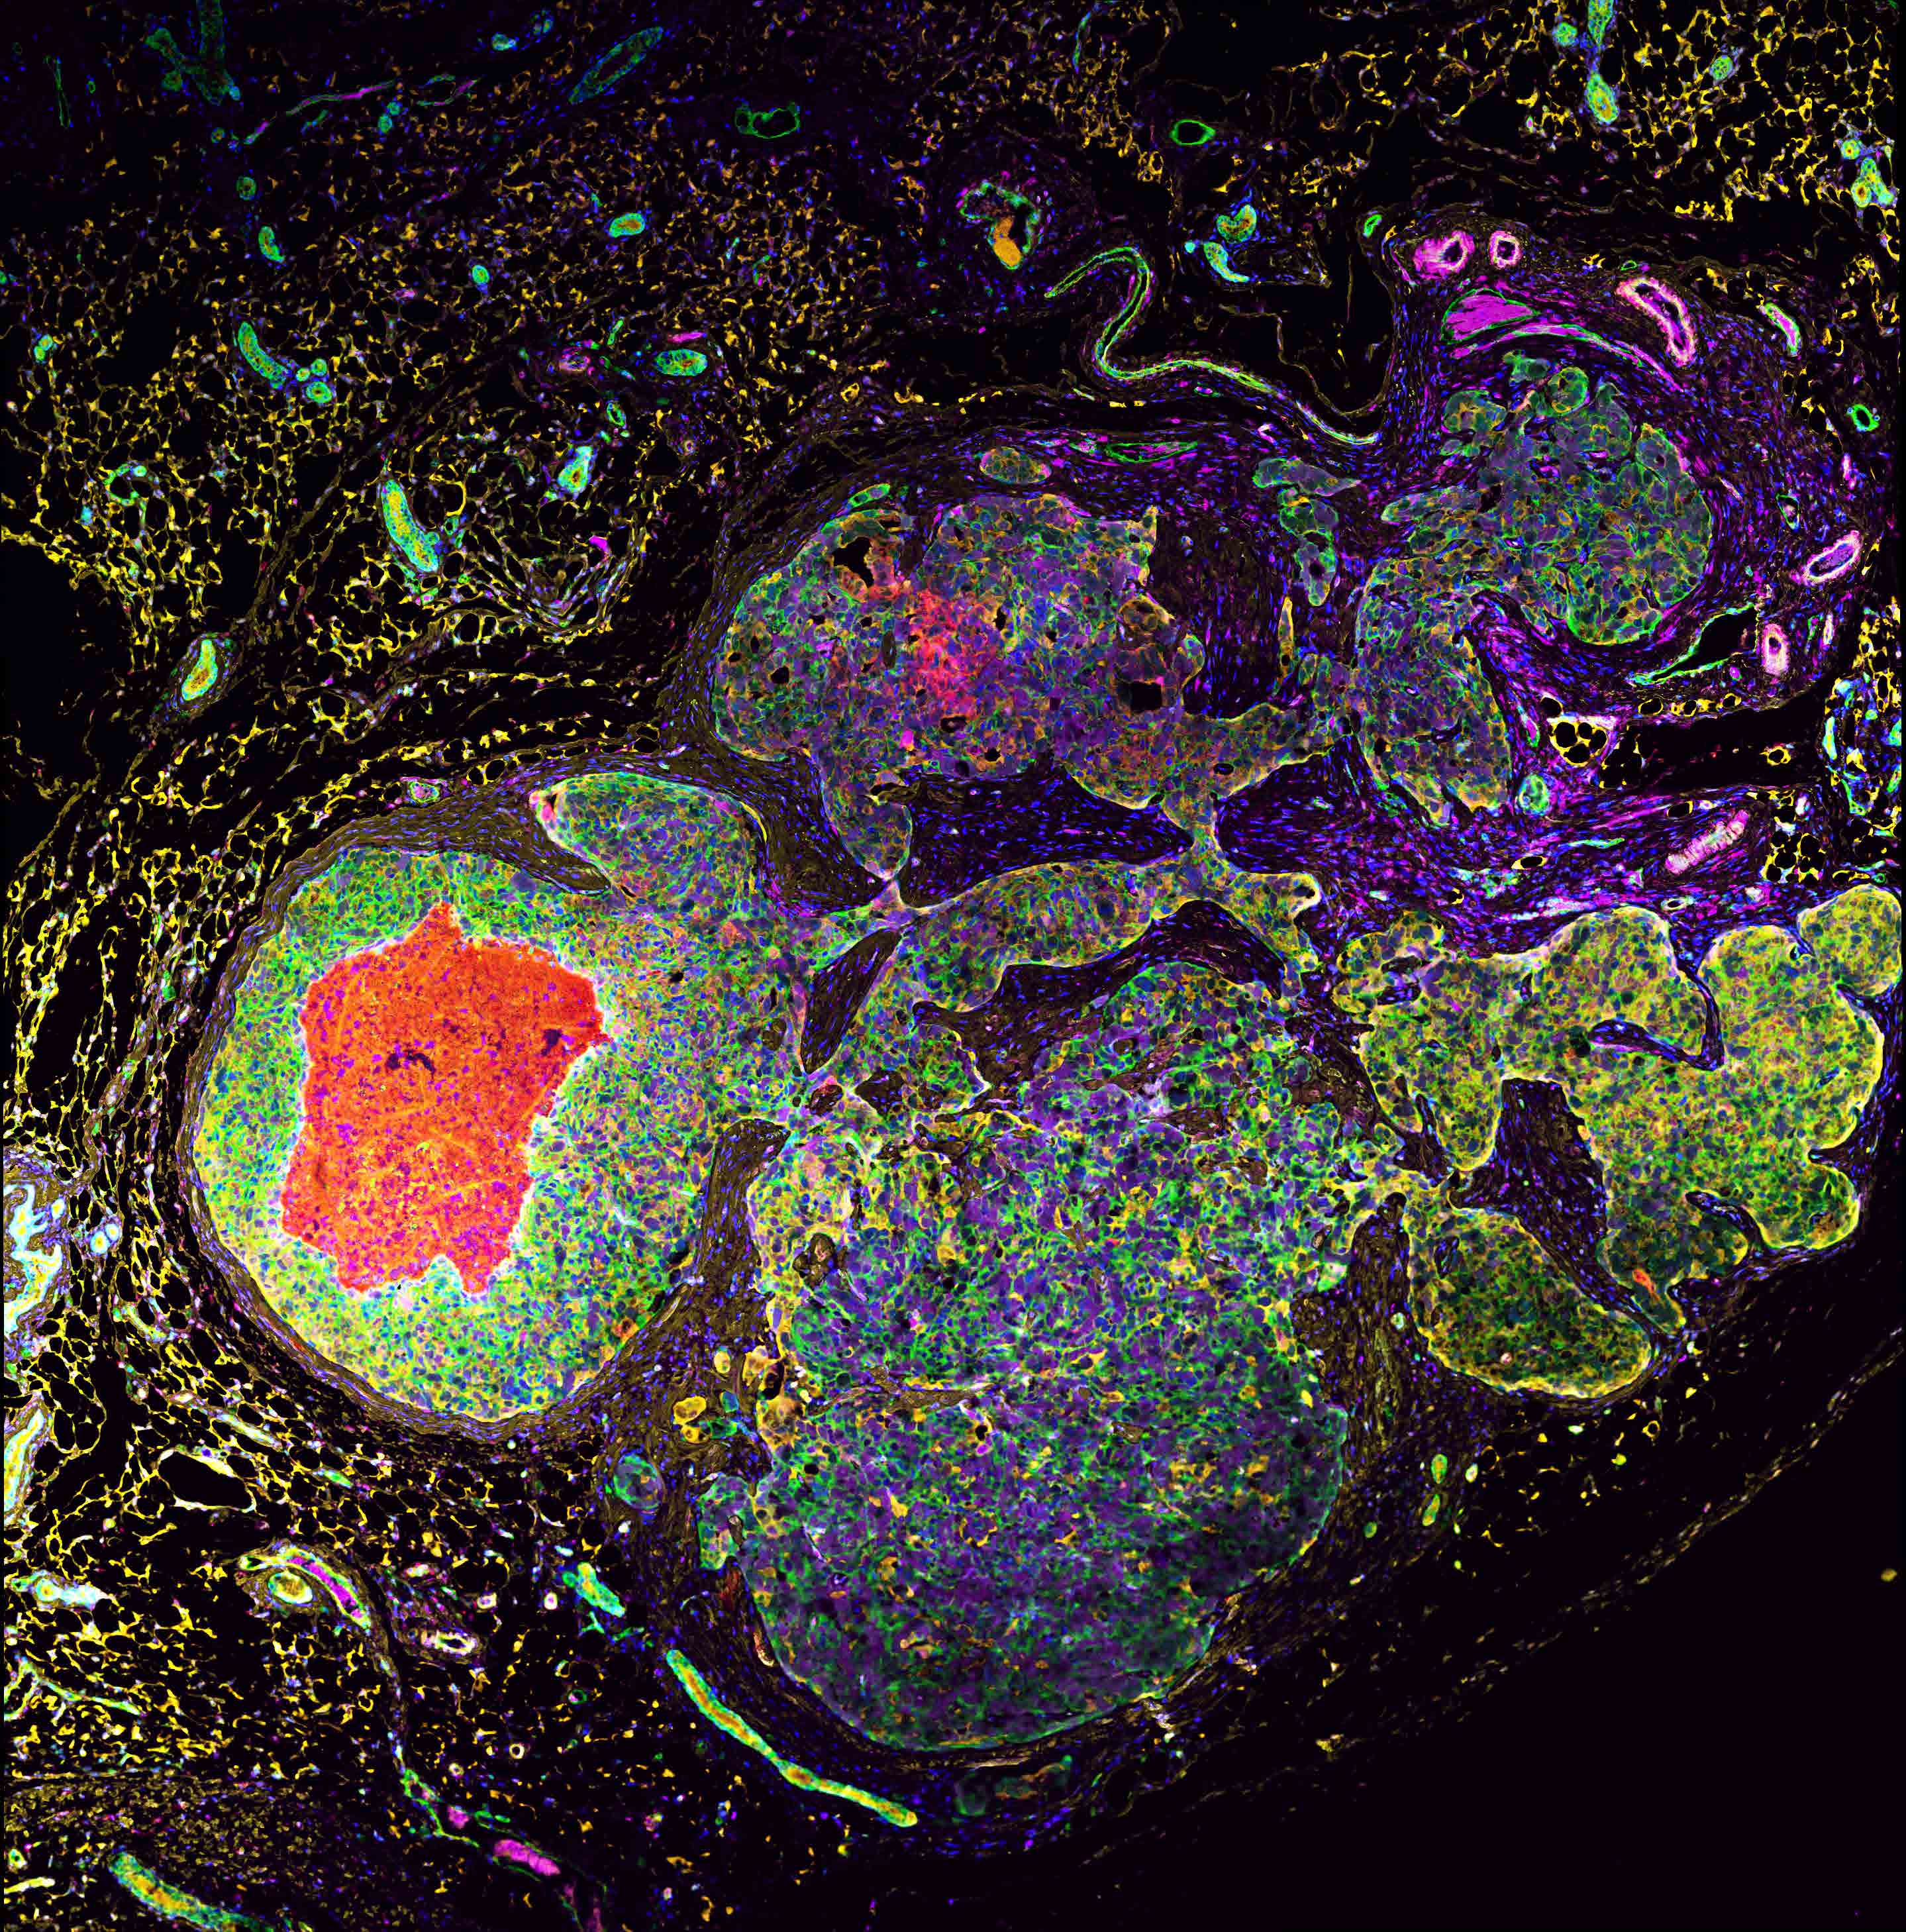

EToH and the GCI are turning the Bellini Atrium into a mini science-meets-art gallery and we’d love for you to be part of it. Whether it’s a stunning histology image, a journal cover, a creative data visualization, or an artistic take on your research, this is your chance to share your work in a new light.